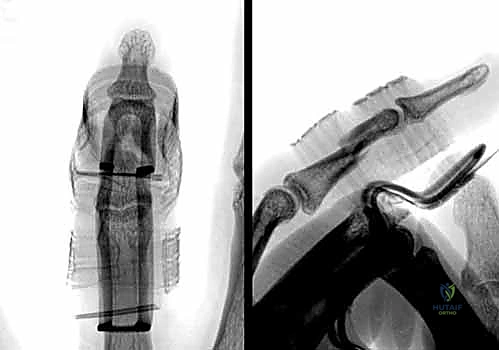

1. الرد المغلق والتثبيت بأسلاك كيرشنر (CRPP - Closed Reduction and Percutaneous Pinning):

تُعد هذه الطريقة الأقل توغلاً. يقوم الدكتور هطيف برد الكسر يدوياً تحت توجيه جهاز الأشعة السينية المباشر (C-arm) في غرفة العمليات، ثم يقوم بإدخال أسلاك معدنية دقيقة (K-wires) عبر الجلد لتثبيت العظم.

* المزايا: لا تتطلب شقاً جراحياً كبيراً، تحافظ على الإمداد الدموي للعظم، وتقلل من خطر التصاقات الأوتار.

* العيوب: تتطلب إبقاء جزء من السلك خارج الجلد (عادةً)، مما يستلزم إزالتها في العيادة بعد 4-6 أسابيع.